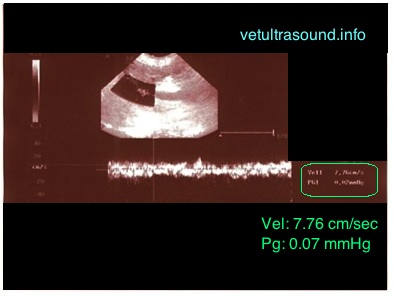

Φυσιολογικά στο σκύλο, η ταχύτητα στην πυλαία φλέβα πρέπει να είναι μεταξύ 10 – 25 cm/sec και η κυματομορφή να είναι με κατεύθυνση προς το ήπαρ με ήπια παλμικότητα η οποία ακολουθεί τον αναπνευστικό ρυθμό. Οποιαδήποτε αλλαγή από το φυσιολογικό μπορεί να σημαίνει πως υπάρχει κάποιο ηπατικό ή καρδιολογικό πρόβλημα. Στην συγκεκριμένη περίπτωση, στην παραπάνω εικόνα, η ταχύτητα είναι μειωμένη και κυματομορφή δεν είναι σταθερή.